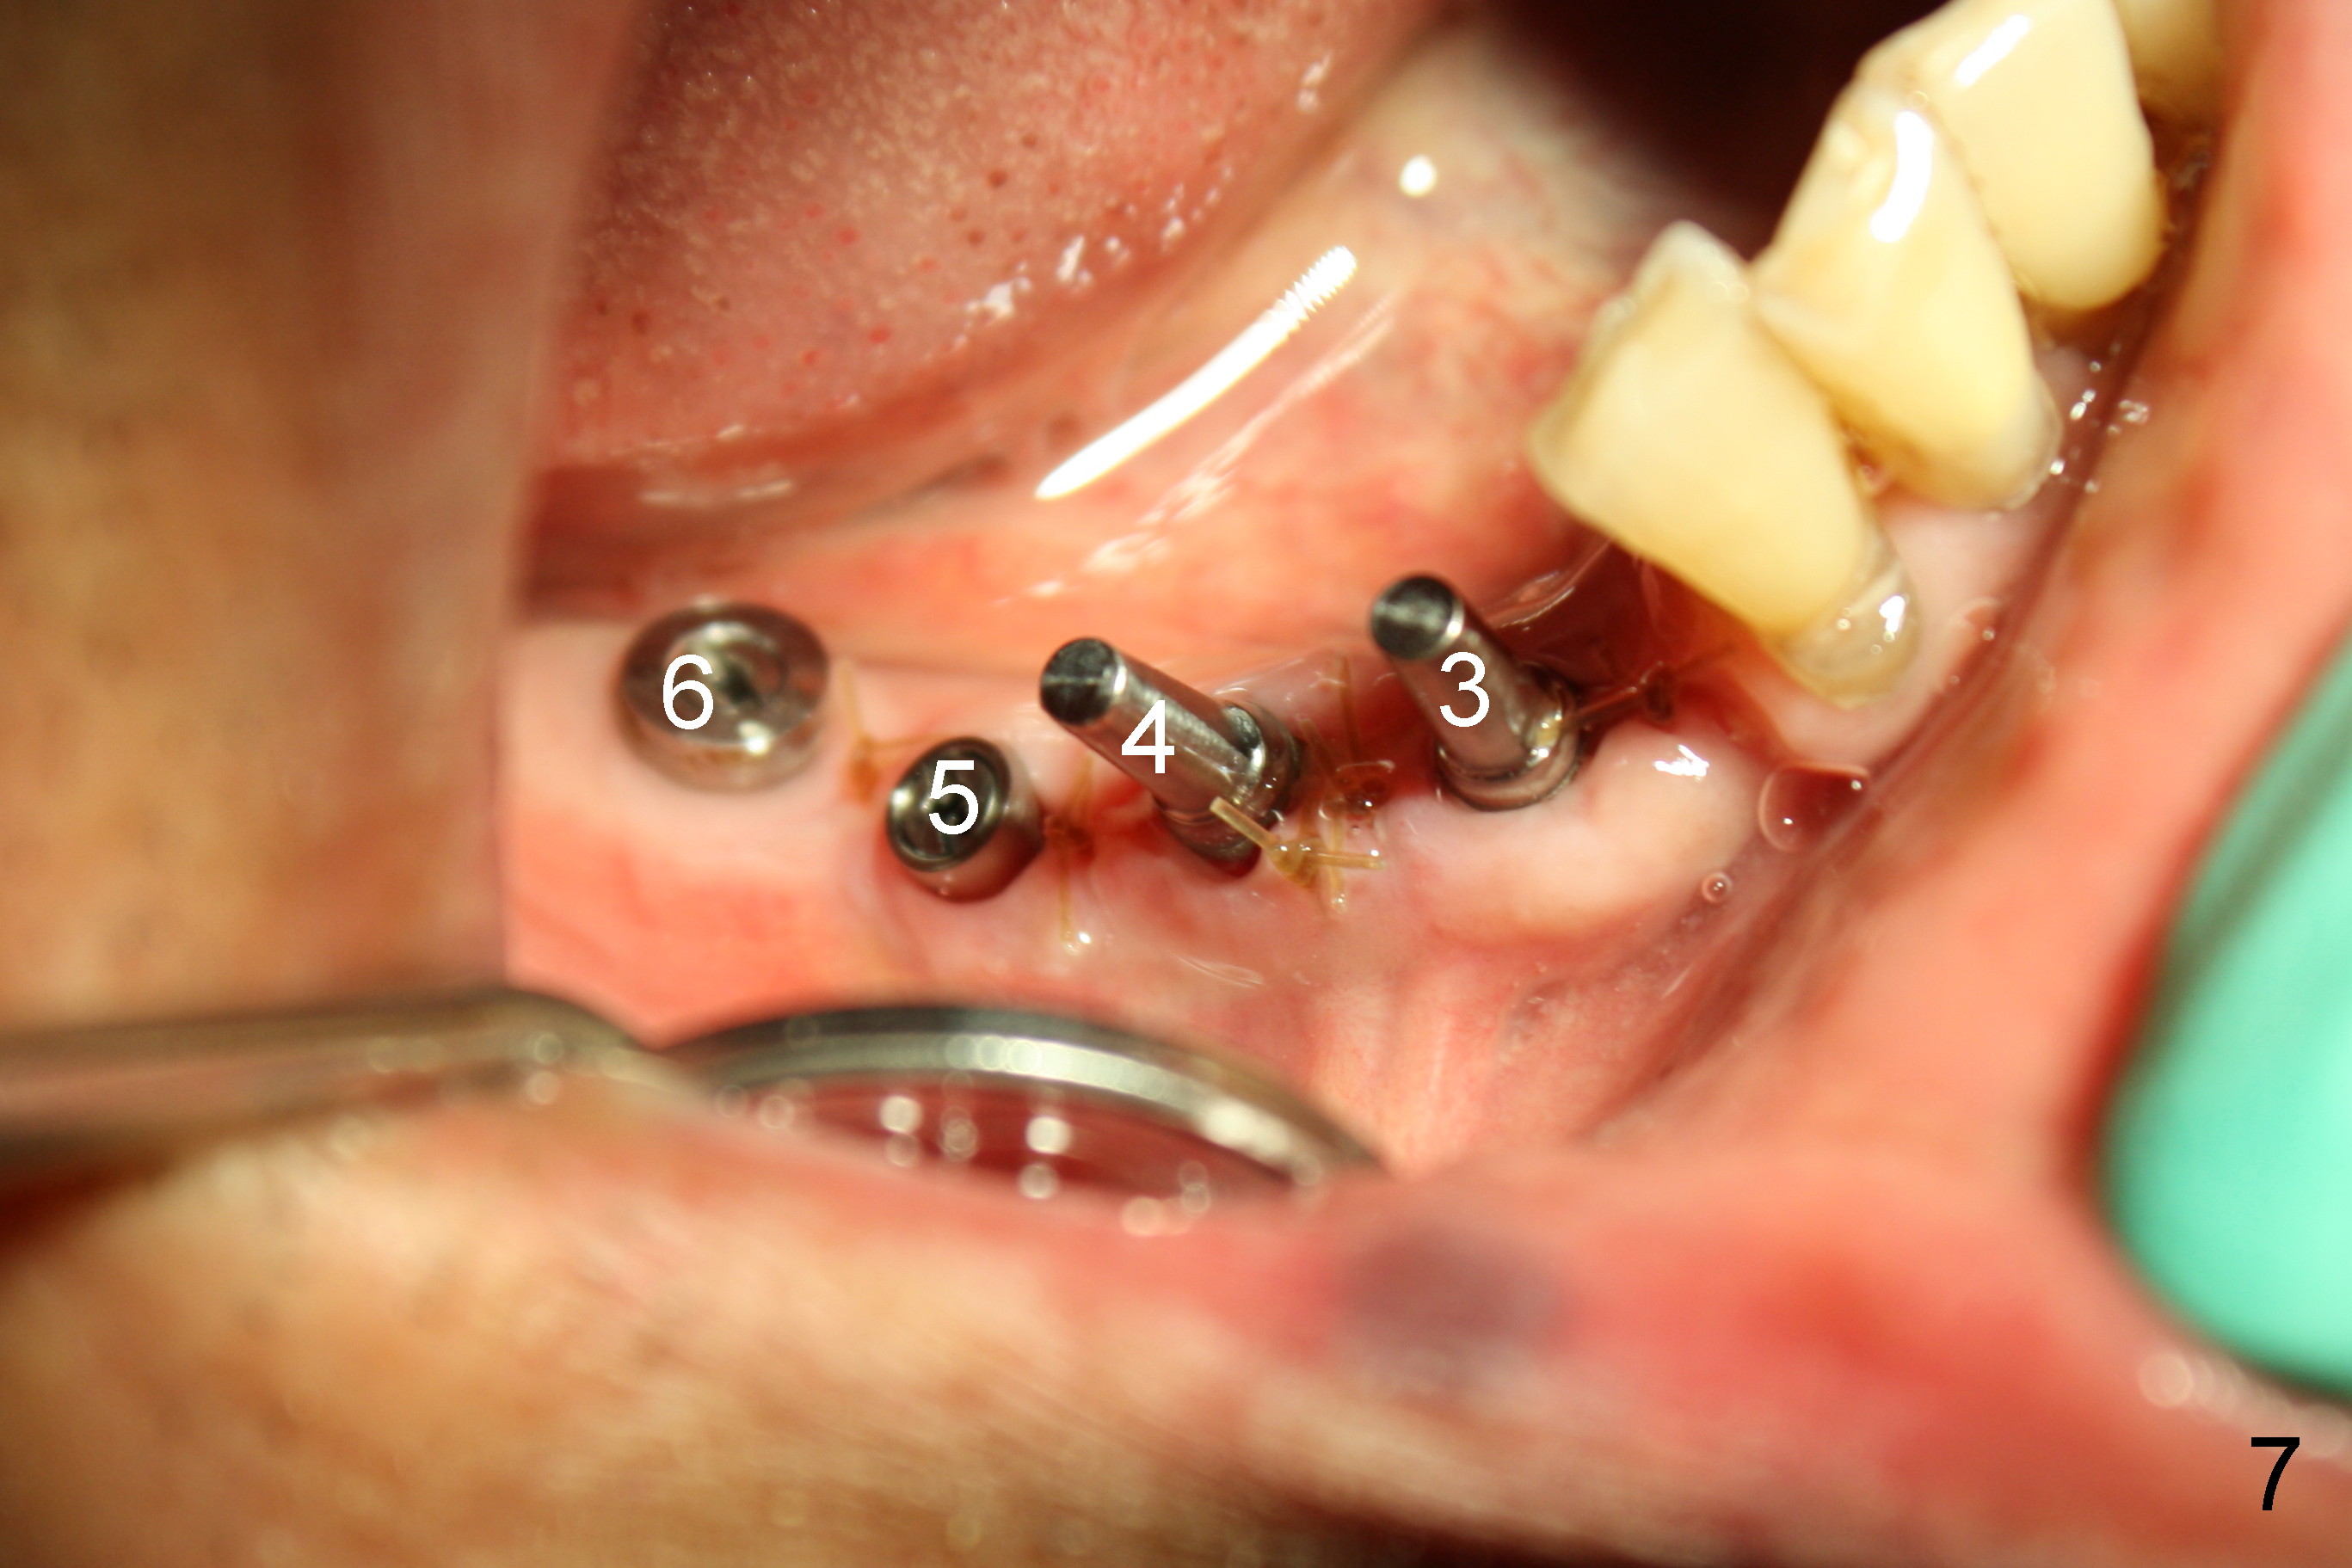

The lower right bridge (from canine (Fig.2: 3) to 1st molar (Fig.1: 6)) fails while a 77-year-old man is undergoing chemotherapy for urinary bladder cancer.  The abutments of the bridge are extracted without plan for implants (Fig.4).   Four months later, the patient returns for implants (Fig.3), but the ridge is narrow (Fig.5).  While 2 of 3x14 mm 1-piece implant are placed at the canine and 1st bicuspid sites, 2 piece ones at the 2nd bicuspid and 1st molar sites (Fig.6: 3.5x11 mm, 5x14 mm).  Soft (Fig.7-10) and hard (Fig.11) tissues heal 1 week (Fig.7) and 4 months (Fig.8-11).  There is minimal bone resorption 1 year 7 months post cementation (Fig.12,13, non-splinting).  It appears that narrow diameter implants are a valid solution to narrow ridge at the sites of the lower canine and premolar.  As long as there are enough implants for function, the crowns are not necessary to be splinted.  Surprisingly, the patient starts flossing after implant restoration.  Retrospectively an immediate provisional bridge should have been fabricated.